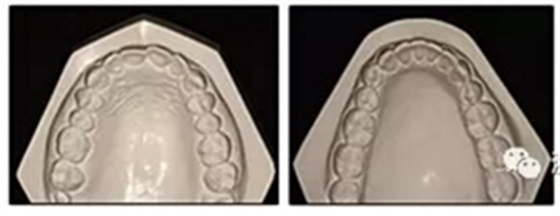

圖2. 治療前牙齒石膏模型

患者決定采用非手術(shù)治療方法,側(cè)貌沒(méi)有任何預(yù)期的變化。治療后面部照片(圖5)顯示她改善的微笑和側(cè)貌,包括尖牙保護(hù)合。由于先天性第一前磨牙缺失,右磨牙關(guān)系為III類。治療后牙齒石膏模型(圖6)顯示實(shí)體牙齒交錯(cuò)排列情況,并且全景X線片顯示可接受的牙根平行度而且沒(méi)有牙根吸收表現(xiàn)(圖7)。最終的頭影測(cè)量片(圖7)證實(shí)了面部評(píng)估,并且描跡圖顯示深覆蓋的改善,同時(shí)保持上頜切牙位置并通過(guò)測(cè)量ANB角度和Wits評(píng)估改善骨性II級(jí)關(guān)系(表)。治療前后的疊加圖顯示由于下頜切牙前傾的增加改善了下唇平衡(圖8)。如相關(guān)治療計(jì)劃所預(yù)測(cè)的那樣,B點(diǎn)出現(xiàn)。A進(jìn)行牙科錐形束計(jì)算機(jī)斷層掃描以記錄下頜前牙區(qū)的骨質(zhì)變化。如預(yù)期的那樣,由于治療導(dǎo)致該區(qū)域的骨量增加(圖9)。